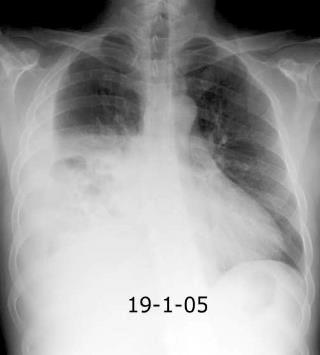

Marzo 2014: Perforación longitudinal distal secundaria a episodio de vómito (síndrome de Boerhaave). Derrame pleural izdo. que evoluciona a empiema.

Wang C-T et al. Tension hydropneumothorax in a Boerhaave syndrome patient: A case report . World J Emerg Med, 2021. Katabathina V et al. Nonvascular, nontraumatic mediastinal emergencies in adults:a comprehensive review of imaging findings. Radiographics. 2011.